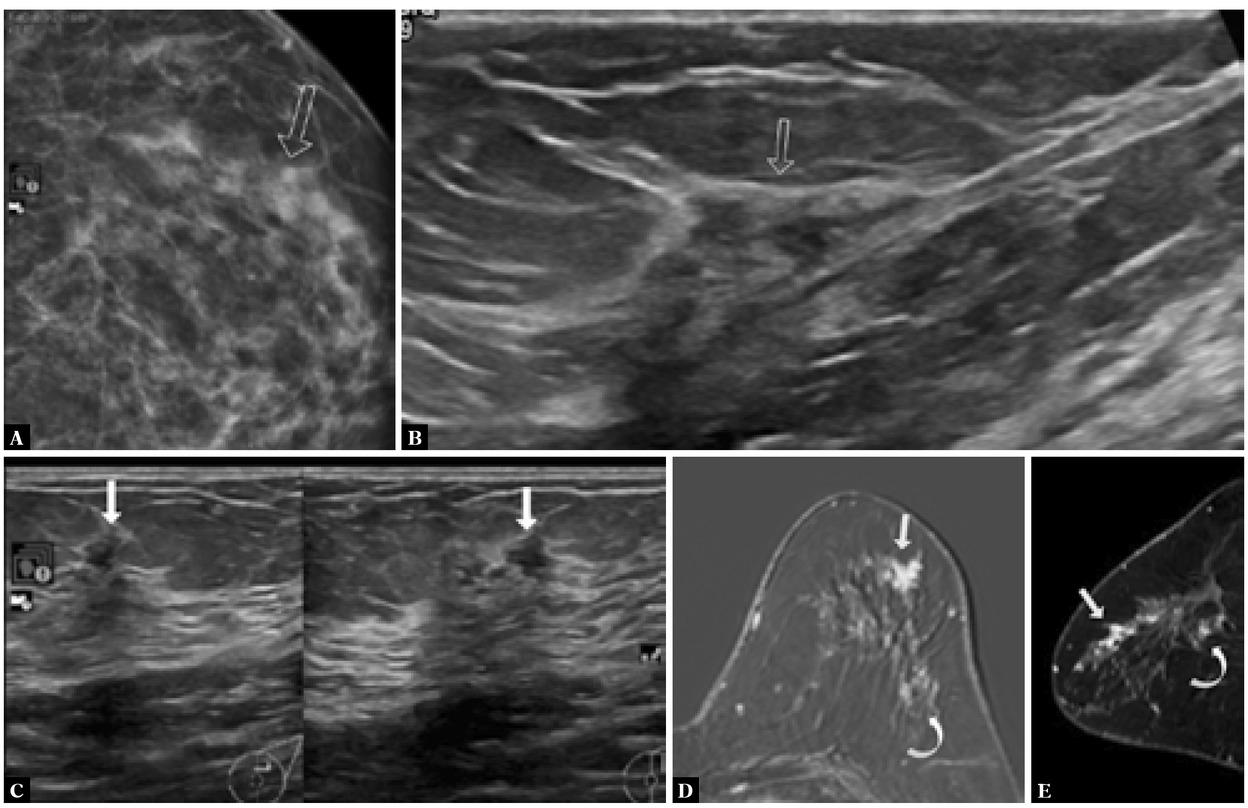

Fig. 2

A. Mammogram LMCC showed post-operative scarring in the upper outer left breast. Developing asymmetry with suspicious linear calcifications at and just anterior to the scar, measuring 1.2 × 0.4 cm. B. Ultrasound showed post-operative changes in the upper outer left breast with a subtle small hypoechoic lesion close to the surgical scar in the upper outer left breast (2:00–3:00) measuring less than 1 × 1 cm (arrow). C. Another subtle irregular hypoechoic mass with adjacent shadowing and a few tiny hypoechoic lesions (abnormal duct-like appearance) at periareolar 1:00, may correlate with mammographically seen calcifications and measures 1 × 0.5 cm. D. MR showed non-mass enhancement at 1:00 in the left breast (solid arrow) and non-mass enhancement at the scar in the posterior third of the upper outer left breast (curved arrow). E. Reconstructed sagittal MR image shows non-mass enhancement in the upper outer left breast (solid arrow) and few enhancing foci close to the scar in the deep upper outer breast (curved arrow)